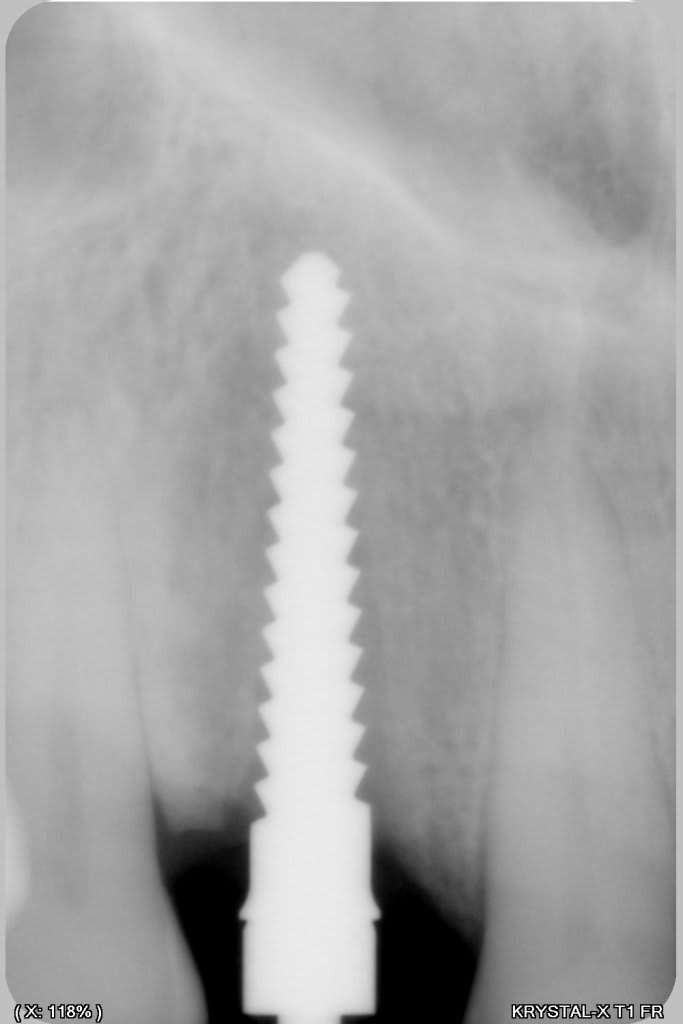

Manipulation de la paroi palatine, afin de déplacer la moitié de l'os en vestibulaire, et pose d'un Px (Anthogyr) utilisation, de lame 11, ostéotome demi lune de Tatum, spreader (Meissinger) et divers.

Le plus bluffant quand tu fais défiler les photos c’est que tu passes de la dernière (avec l’implant en place) à la 1ere avec la fenestration!

de mémoire un PX 34100 ou 34120

effectivement, mais c'est un des avantage de l'expansion, mais dans ce cas là, il y aura largement les 2mm, l'os déplacé en vestibulaire permet de "fermer la boite " qui avait déjà 3 belles parois.